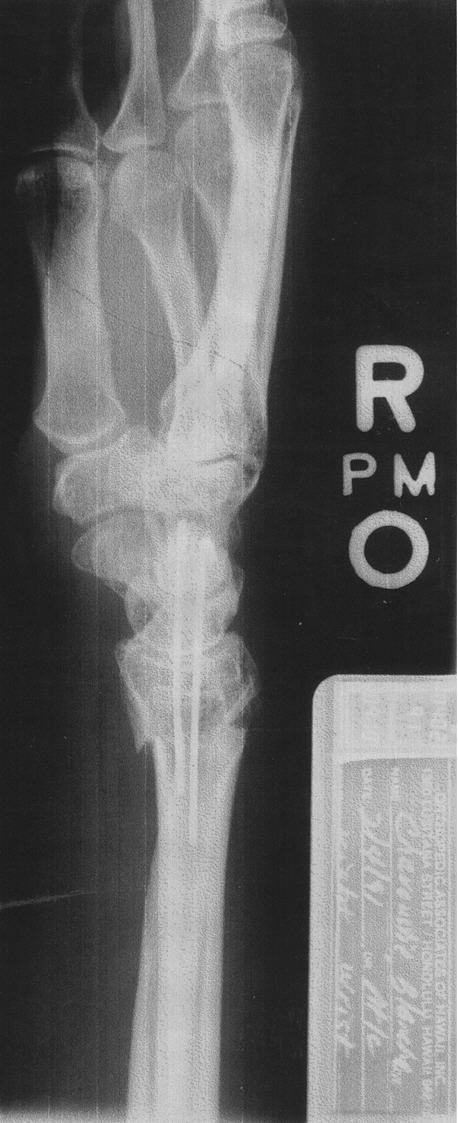

Xray

You can see the wire in my ankle very well. It looks like an M. However, you cannot see the two eggshape implants that are in my big toe because the x-rayis too dark. They do show very clearly but they do not copy well. Would you like me to snail mail a photo copy of the xray which has the egg shape implants drawn in?

The x-ray is very readable but it prints so dark that the implants in the toe don't show in computer files. The two white egg shapes in the toe are exact tracings of the implants which are embedded into the bone.